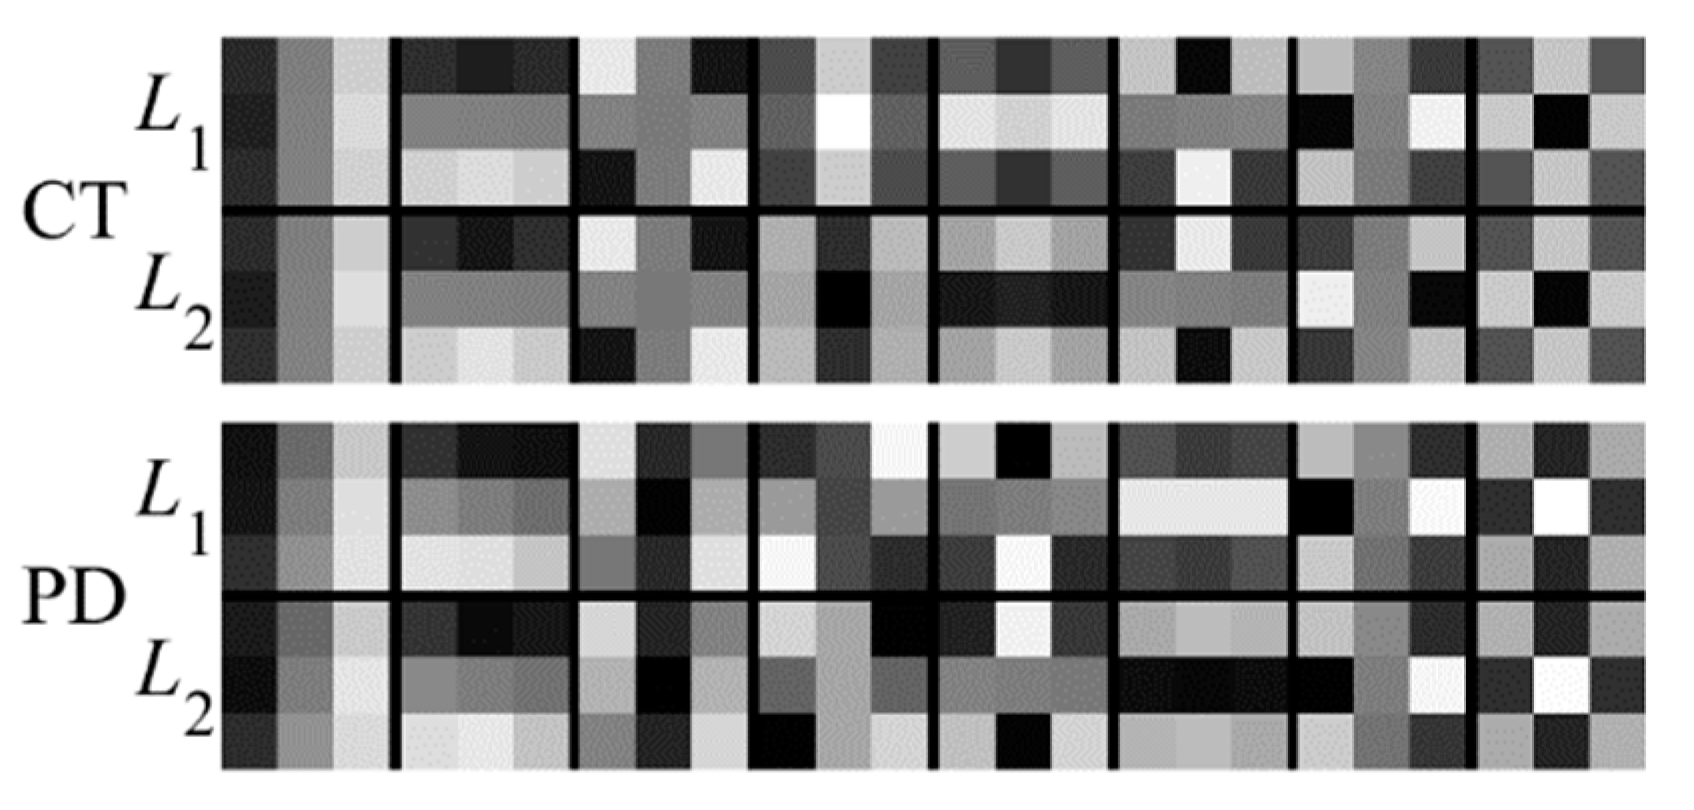

2.1. Structure of the Improved PCANet

2.1.1. The First Stage of PCANet

2.1.2. The Second Stage of PCANet

2.1.3. Output Stage

2.2. Structural Representation